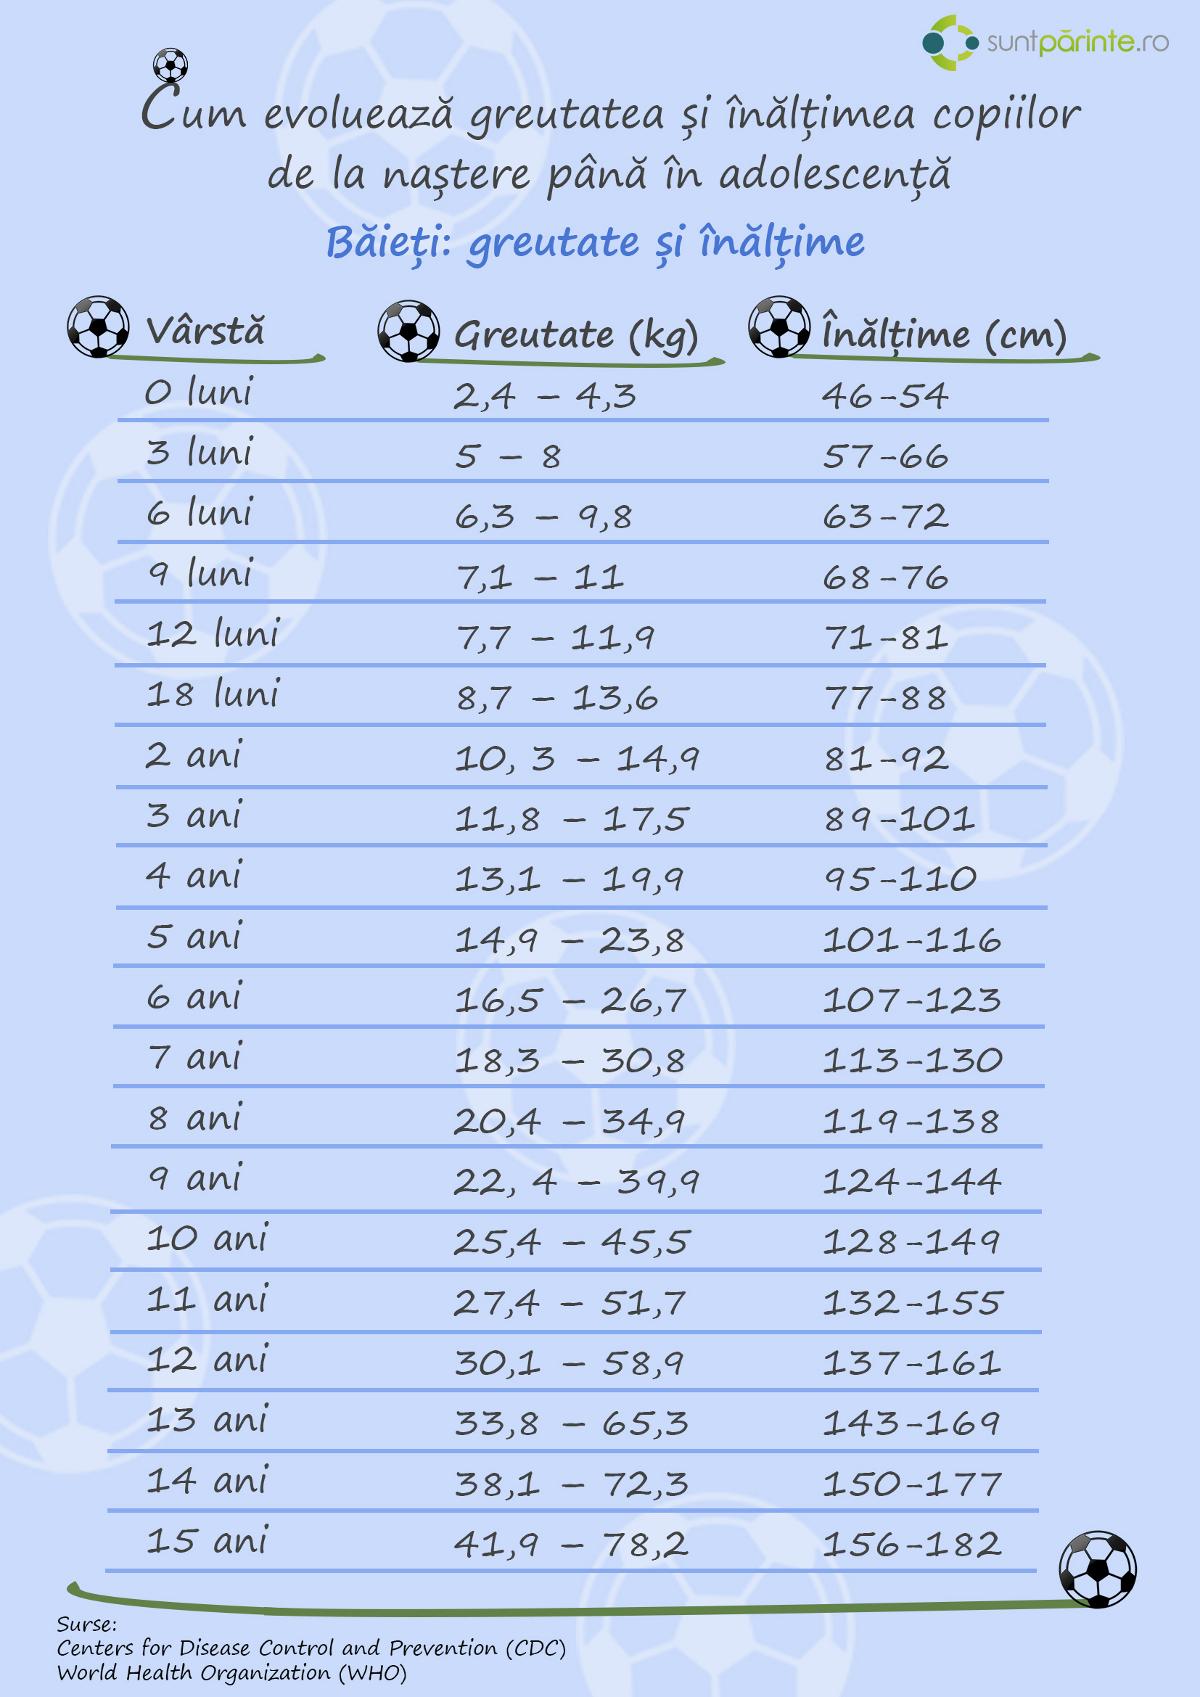

Semnele care pot sugera dificultăți în creștere sunt adesea variate și pot fi subtile; monitorizarea atentă a evoluției staturo‑ponderale, a apetitului și a reperelor de dezvoltare poate ajuta la identificarea timpurie a unor probleme. Observațiile precum scăderea ritmului de creștere față de curbele obișnuite, pierderea sau stagnarea în greutate, oboseala persistentă ori întârzieri în abilitățile motorii şi lingvistice nu confirmă în sine o afecțiune, dar pot indica necesitatea unei evaluări mai detaliate.

Dacă observați o schimbare persistentă în ritmul de creștere – de exemplu scăderea constantă a poziției pe curba de creștere sau o diferență semnificativă față de istoria familială – este rezonabil să solicitați o evaluare medicală. Alte semne care pot justifica o consultare includ apariția timpurie sau întârziată a semnelor pubertare, oboseală severă, pierdere inexplicabilă în greutate sau dureri persistente; aceste manifestări pot necesita investigații suplimentare pentru a identifica cauzele și opțiunile de susținere.

Evaluarea clinică se bazează pe o anamneză detaliată şi examen fizic atent, incluzând observarea aportului alimentar, istoricul familial de creştere şi măsurători antropometrice standardizate. Măsurători precum greutatea, înălţimea/ lungimea şi perimetrul cranian urmărite pe grafice de creştere permit identificarea unor tendinţe; o singură valoare izolată oferă mai puţină informaţie decât evoluţia în timp. Contextul dezvoltării neuro‑motorii şi semnele clinice asociate pot oferi indicii despre posibile cauze şi ce investigaţii pot fi considerate.

Monitorizarea ar trebui să fie consecventă şi orientată spre identificarea schimbărilor de traiectorie, deoarece o rulare susţinută în sus sau în jos pe percentile poate necesita reevaluare. Colaborarea multidisciplinară cu medicul de familie/pediatru, nutriţionist sau alţi specialişti poate contribui la stabilirea unui plan individualizat de urmărire; investigaţii suplimentare pot fi indicate atunci când există semne de alarmă sau dacă tendinţa nu se normalizează. Pentru resurse suplimentare vedeţi creștere. Atenţie: orice îngrijorare legată de ritmul de creştere trebuie discutată cu un specialist.